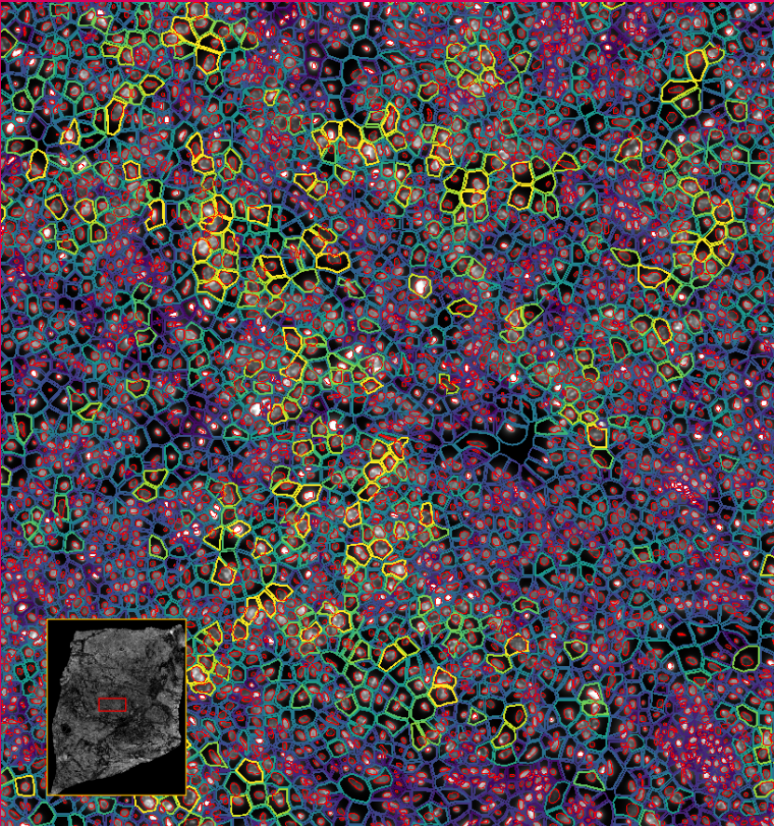

ͼ4-1£ºÊ¹ÓÃDAPI¶Ôϸ°ûºËȾɫ£¬£¬£¬£¬£¬£¬£¬ÍŽáÉî¶ÈѧϰҪÁìÍÆ¶ÏÍêÕûµÄϸ°û½çÏß

ͼ4-2£ºÊ¹ÓÃDAPI¶Ôϸ°ûºËȾɫ£¬£¬£¬£¬£¬£¬£¬ÍŽáÉî¶ÈѧϰҪÁìÍÆ¶ÏÍêÕûµÄϸ°û½çÏß